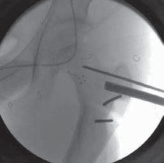

3. The level of the transverse osteotomy is marked on the bone with a marking pen or cautery. This is done about

1 to 1.5 cm below the level of the seating chisel, at the upper end or just proximal to the lesser trochanter (

TECH FIG 3A

).

4. The periosteum is elevated circumferentially at this level to allow placement of protective retractors during the osteotomy.

5. Two smooth pins (2.5-mm Kirschner wires) are placed in an anterior-to-posterior direction parallel to each other and perpendicular to the long axis, just proximal and distal to the proposed osteotomy site respectively (

1. These two pins will serve as useful retractors of the vastus lateralis muscle anteriorly, and as joysticks to retain effective control of the proximal and distal segments after the osteotomy.

2. At the time of the derotation, the angle between the distal and proximal pins accurately gauges the magnitude of correction obtained and maintained during fixation of the blade plate.

6. The transverse osteotomy is completed with an oscillating saw directed perpendicular to the long axis of the femur and parallel to the seating chisel above (

TECH FIG 3B,C

TECHNIQUES A B CTECH FIG 3 • Completion of transverse osteotomy, derotation, and fixation with 90-degree blade plate.A. Level of the osteotomy is at upper end of the lesser trochanter 1.5 cm below the seating chisel. Two parallel AP guide pins proximal and distal to the osteotomy line are used to judge the magnitude of derotation. B,C. Transverse osteotomy parallel to the seating chisel and perpendicular to the long axis of the femur. lated, which necessitates removal of the guide pin (in addition to the seating chisel) at the time of insertion of the blade plate, which removes an important guide for its introduction.